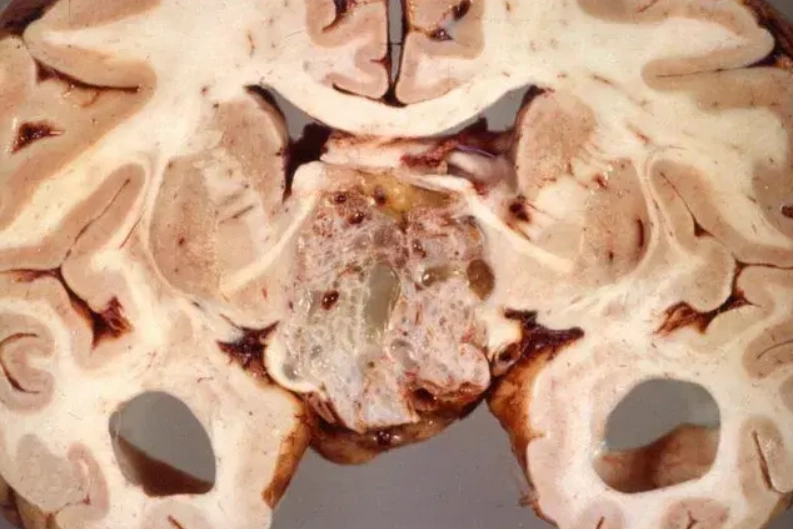

• U sọ hầu dạng Adamantinoma (Adamantinomatous Craniopharyngioma)